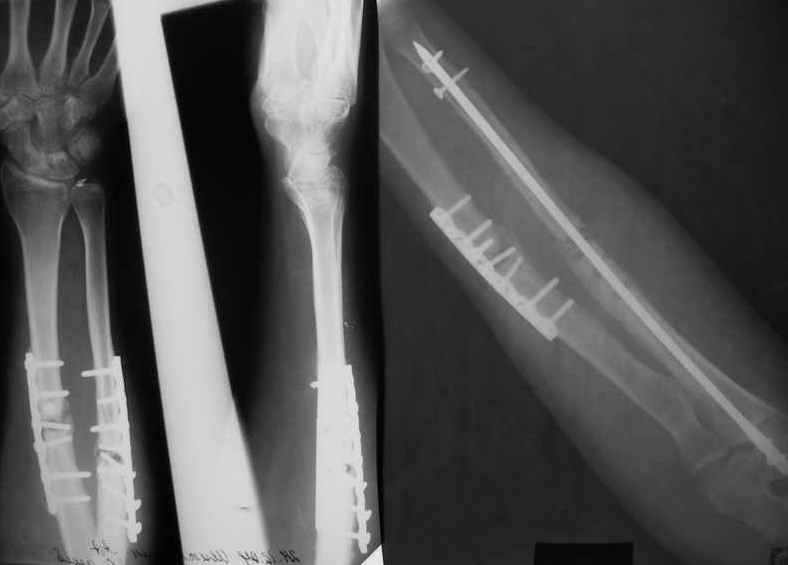

Уважаемые коллеги!Доводим до Вашего сведения наш скромный опыт применения блокирующего остеосинтеза локтевой кости (4случая), четверо пациентов с ложными суставами локтевой кости. Во всех случаях оперировали открыто с костной аутопластикой.Технических проблем введения штифтов не было. В одном случае отвалилась резьбовая часть спицы при прокс. блоке (оставлена как блокирующий винт). Дистальное блокирование осуществляли используя вместо кондуктора сп. Киршнера изгибая ее конец о край кондуктора на необходимую длину до отверстий. Наши первые впечатления классные. Очень быстрая функциональная реабилитация без гипса и консолидация через 2 мц. На представленных фотографиях двое пациентов.Тот, у которого якобы не срастается лучевая кость на АО пластине, уже катался на горн. лыжах, а сейчас опять уехал на Эльбрус -экстремал ,,,нов. С уважением Нагога Александр, ортопедическая клиника ОРТО, Самара.

Считаю нецелесообразным применение штифтов при переломах костей предплечья при острой травме, а тем более при несращениях.Правильный остеосинтез при ложных суставах пластинами LC-DCP или LCP с костной аутопластикой даёт прекрасные результаты и возможность ранних активных движений.Кроме того,гвоздь нарушает анатомическую конфигурацию костей что ведет к несращению другой.

Положим, *правильный* интрамедуллярный дает то же самое, причем закрыто, и разрезы по 0,5 см. А если еще вспомнить про рефрактуры после удаления пластин, чего не бывает при удалении стержней?

А зачем же неправильный гвоздь использовать, который нарушает? Наоборот, с помощью гводя нарушенная форма костей очень даже эффективно восстанавливается (см. пример). А неправильный

остеосинтез можно сделать чем угодно.